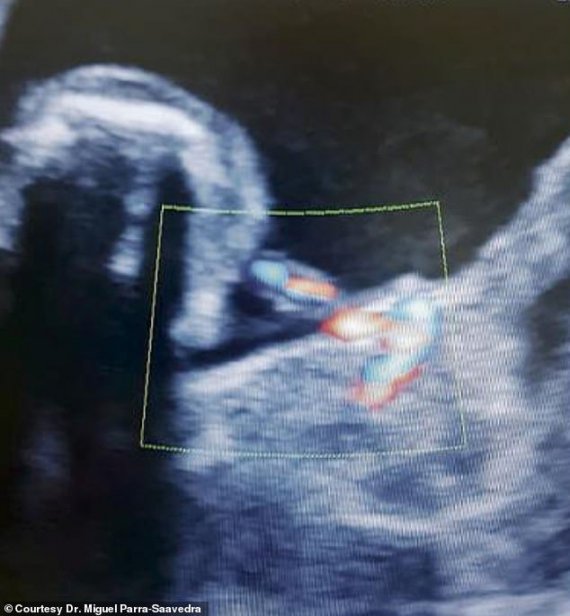

Виявили аномалію лікарі під час УЗД, проведеному на 35-му тижні вагітності. На той момент знайдене новоутворення сприйняли за кісту печінки й порекомендували жінці звернутися до фахівця з ведення ускладнених вагітностей. Спеціаліст провів повторне сканування на сучаснішому обладнанні. Це була 3D/4D ультразвукова допплерографія — обстеження, яке дозволяє побачити кольорове зображення кровоносних судин. У результаті в череві дівчинки виявили 44-міліметровий плід. Його пуповина була прикріплена до кишечнику дитини, пише відоме британське видання Dailymail.